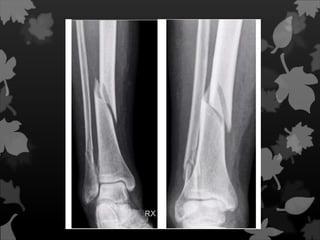

Fratura Segmentar

Fratura dupla

com duas linhas

de fratura, que

isola um

segmento

distinto do osso;